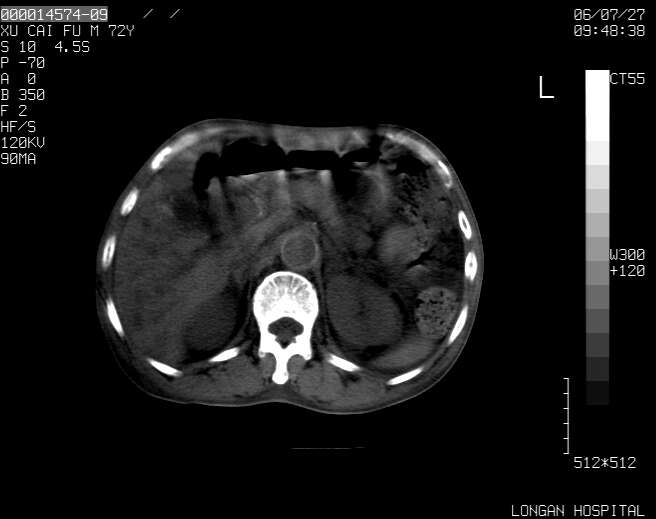

以下是引用winter在2006-7-30 20:14:00的发言:[br]1、考虑胆囊癌伴胆道侵犯并高位胆道梗阻、肝内多发转移、腹膜后淋巴结转移。[br]2、右肾轻度积水。[br]3、老人家72岁了胰腺头体尾部均较饱满,不过未见密度异常及其他异常征象。[br]4、腹水。

以下是引用jiajie在2006-7-31 7:10:00的发言:[br]考虑肝转移瘤,腹膜后淋巴结增大。[br]胃癌不能除外,建议胃镜检查。